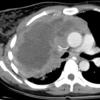

lymphoma (NHL) axial CT

Rt supraclavicular nodes